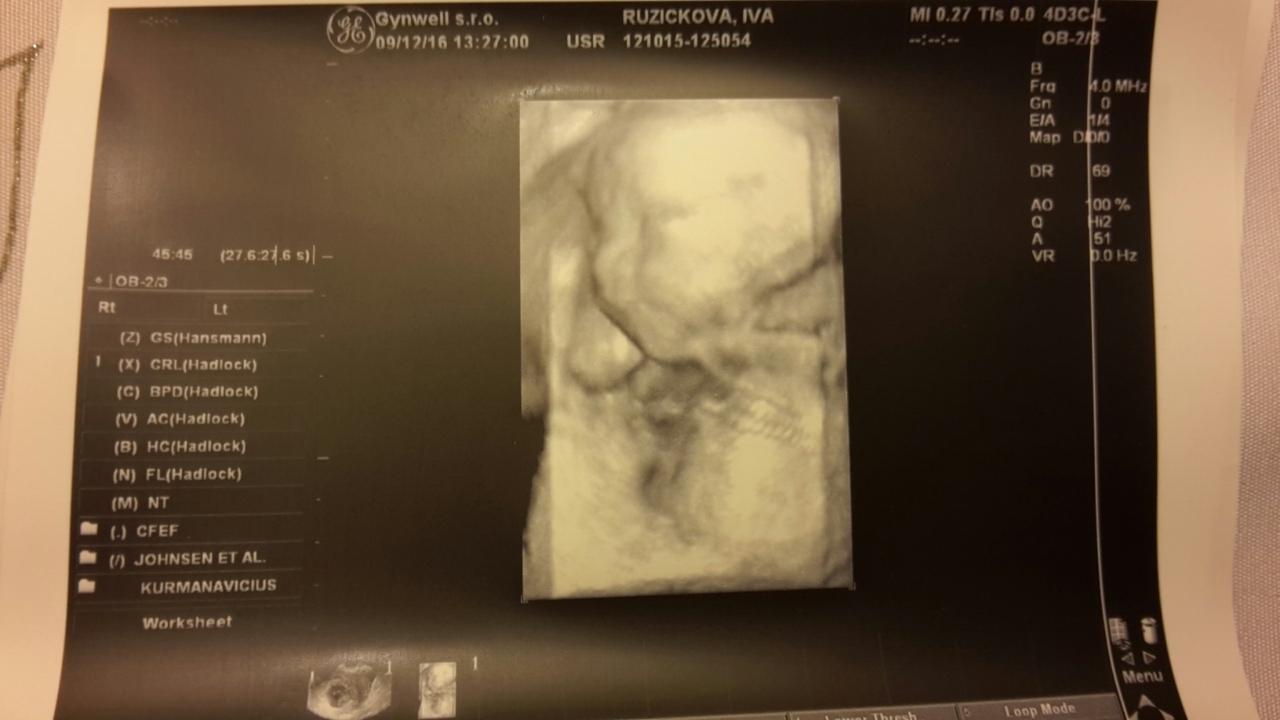

Krásné fotečky a jak ti je? 🙂